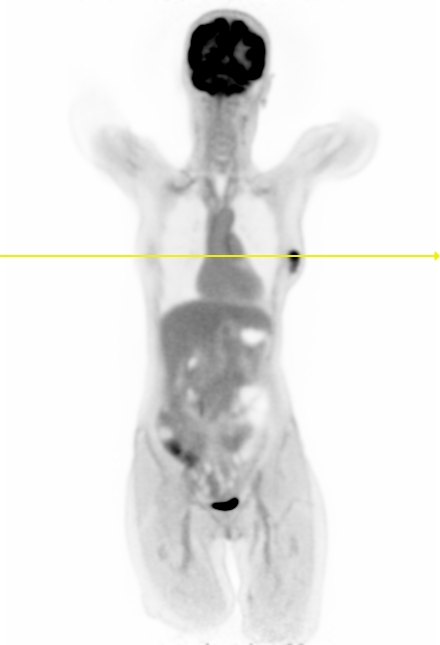

Figure 7 shows three clinical \acFDG dataset examples. The \acDLSE-corrected images are visually very similar to the \acSSS-corrected images. Examining the profile lines in the first row, which displays a breast lesion in a female patient, reveals similar patterns to those observed in the simulated images in Figure 4, with lower activity in the region between the lungs using \acSSS compared to \acDLSE. However, the activities within the lesion are very similar for both \acDLSE and \acSSS.

In the second row dataset, \acDLSE provides better contrast on the nodules than \acSSS, showing similar activity levels between the nodules but with a higher activity peak.

The last dataset shows kidney structures in a large morphology patient (98 kg). The \acSSS-corrected image exhibits an overall higher activity than the \acDLSE-corrected image. After manual segmentation of the kidneys and automatic segmentation of its structures using the FLAB algorithm [37], the contrast is found to be slightly higher in the \acDLSE corrected \acPET images. The contrast is 2.3 with \acDLSE correction, compared to 2.2 with \acSSS correction and 1.8 in the uncorrected image.

| No correction | DLSE | SSS | Profiles |

![]() |

| Sex | Weight | Dose | Coincidences | |

| 1st row | Female | 52 kgs | 160 MBq | 3.0 billions |

| 2nd row | Male | 80 kgs | 244 MBq | 4.7 billions |

| 3rd row | Female | 98 kgs | 297 MBq | 3.8 billions |

The study conducted on clinical \acFDG acquisitions demonstrated consistent results for \acDLSE, producing visually comparable outcomes to \acSSS-corrected images (Figure 7). The method appeared to be robust against significant variations in patient morphology, with weights ranging from 52 to 98 kg. In two of the three cases, \acDLSE-corrected images exhibited slightly higher activity levels, while the \acSSS method showed higher activity in the large morphology patient. This discrepancy may be attributed to inaccuracies in the tail-fitting algorithm used to estimate the scaling factor for multiple scatters, as the tails could potentially be too small for larger morphology patients. In all three examples, the lesion contrasts were found to be greater than those obtained with the \acSSS-based scatter correction.